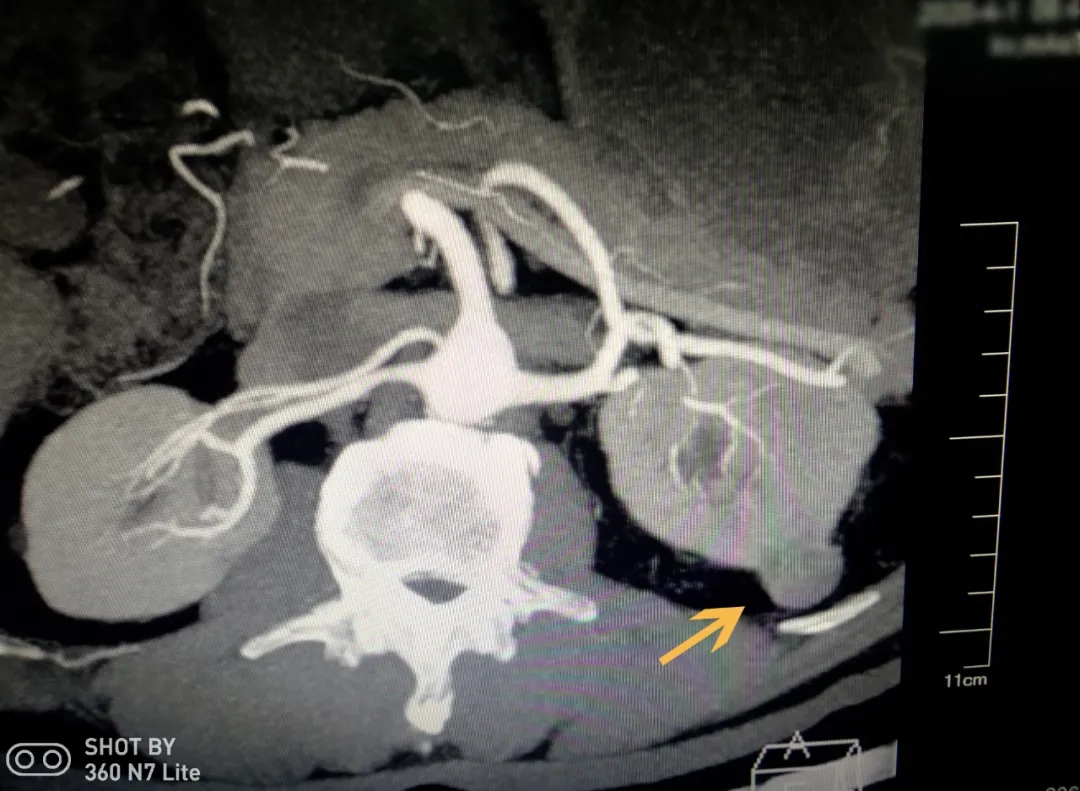

CT检查显示患者左肾有肿瘤